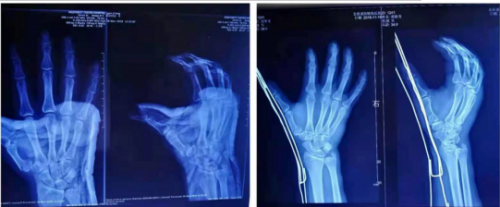

郭某某,男,34岁。2018年11月18日,牡丹江市桦林黄静湖中医馆影像室X光报告右手指第1节骨折端骨折,经传承人黄煜泉采用自制“钢丝牵引架”橡胶条牵引复位,辅助药物治疗。